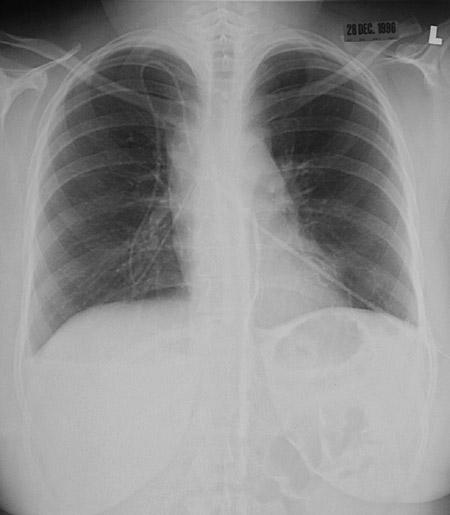

In this PA chest radiograph, the border at superior vena cava is prominent because it is expanded from thrombosis with obstruction in a patient with a hypercoagulable state.